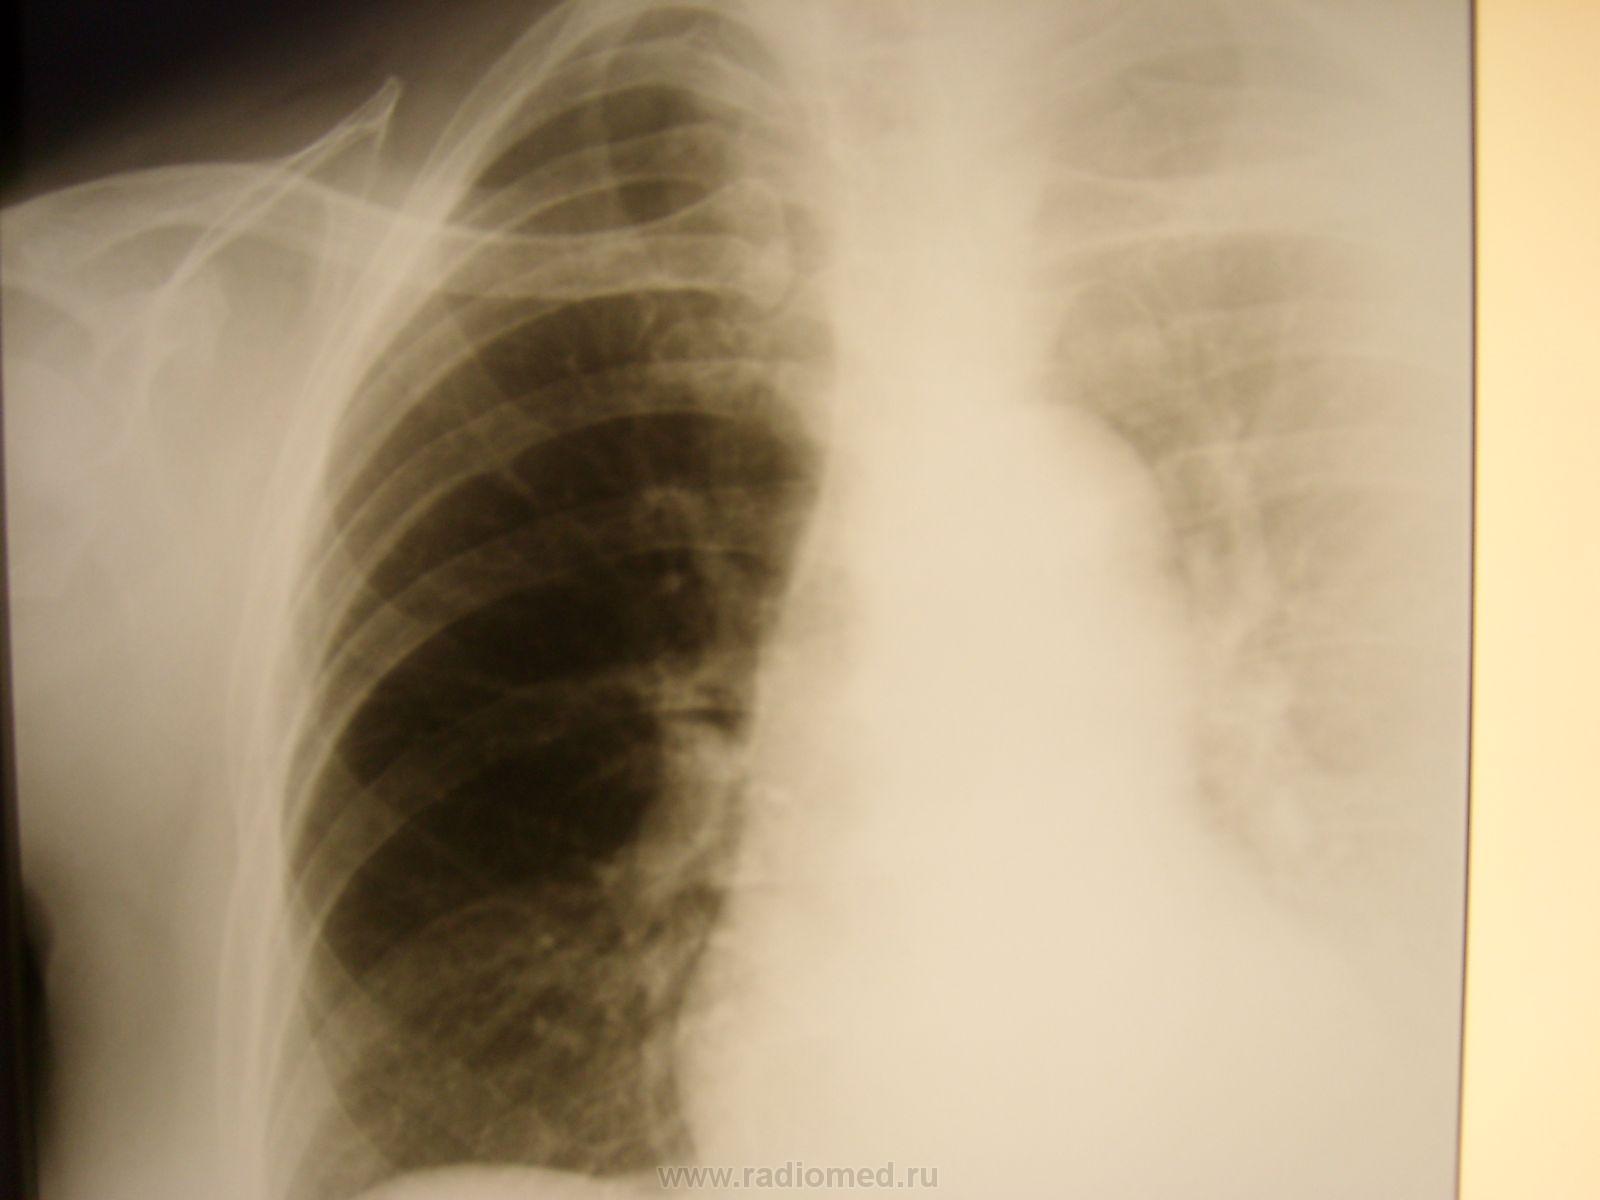

Пол пациента: Женский пол Тип патологии: Травма Область исследования: Грудная клетка и верхние дыхательные пути Методы исследования: Rg Женщина поступила в приёмное отделение после "конфликта" с сожителем https://radiomed.ru/sites/default/files/styles/case_slider_image/public/user/712/sl273142.jpg?itok=k9kzdr31 ID:22279 Втр, 28/09/2010 - 06:16 #1 mila Не на сайте Был на сайте: 5 лет 2 месяцев назад Зарегистрирован: 26.02.2010 - 02:56 Публикации: 277 Не понятно что делали? Если обзорный, почему левое легочное поле срезано? Почему на боковом снимке рука? Втр, 28/09/2010 - 20:39 #2 Глазков Игорь А... Не на сайте Был на сайте: 9 месяцев 1 неделя назад Зарегистрирован: 19.12.2008 - 20:41 Публикации: 1597 проводили для исключения перелома рёбер и пневмогемоторакса Прийди к Себе Ср, 29/09/2010 - 02:47 #3 mila Не на сайте Был на сайте: 5 лет 2 месяцев назад Зарегистрирован: 26.02.2010 - 02:56 Публикации: 277 Певмоторакса нет, руку наверное поднять не может, может перелом плечевого отростка лопатки? Чт, 30/09/2010 - 17:34 #4 Helios Не на сайте Был на сайте: 7 месяцев 2 недели назад Зарегистрирован: 06.08.2010 - 15:16 Публикации: 4417 Ключично-акромиальный сустав еще посмотрите.Каков механизм травмы?Было бы понятнее, что еще можно визуализировать. Сб, 14/07/2012 - 14:10 #5 Махамбетчин Мур... Не на сайте Был на сайте: 3 недели 6 дней назад Зарегистрирован: 14.07.2012 - 10:44 Публикации: 1205 Если это снимок лежа, то больше похоже на гемоторакс слева с незначительным смещением средостения вправо.

проводили для исключения перелома рёбер и пневмогемоторакса

Певмоторакса нет, руку наверное поднять не может, может перелом плечевого отростка лопатки?

Если это снимок лежа, то больше похоже на гемоторакс слева с незначительным смещением средостения вправо.